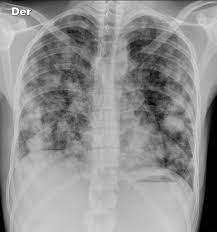

How To Know If Testicular Cancer Has Spread To Lungs / Orchid Results : Lump or swelling in your neck, under your arm, or in your groin.. This is not lung cancer. If testicular cancer has spread to other parts of your body, you may also experience other symptoms. When testicular cancer spreads, it most commonly spreads to the lung and the lymph nodes of the chest, pelvis, and the base of the neck. It's not called lung cancer unless it starts from cells in the lung. Good prognosis means that your primary cancer was in your testicle, or at the back of your stomach or abdomen (retroperitoneal).

The best way to confirm the diagnosis of testicular cancer is to remove the testicle. As others have said this is a type of cancer which does not behave in the same way as most. Swelling and enlargement of male breasts. For example, breast cancer that spreads to the lung is called metastatic breast cancer, not lung cancer. These cancers have spread to a distant lymph node or the lungs. As with other forms of cancer, testicular cancer can spread, or metastasize, to other areas of the body. In stage 3 of the disease, the cancer has invaded other organs such as the lungs, brain or liver. This is testicular cancer which has spread to the lungs. If testicular cancer spreads, it can spread to the following: Which treatment your doctor will choose to treat it is based on the type of cancer you have and if it has spread. Cancer is always named for the place where it starts. So when testicular cancer spreads to the lung (or any other place), it's still called testicular cancer. Liver is pretty close to the lungs.

Headaches or confusion, from cancer spread in the brain. But most of the time they're on the edges of your lungs or in the lower lobes. Swelling of 1 or both legs or shortness of breath from a blood clot can be symptoms of testicular cancer. The tumour has only spread to the abdominal lymph nodes or the lungs or both. Shortness of breath, chest pain, or a cough (even coughing up blood) may develop from cancer spread in the lungs.

Prognostic Factors Of Metastatic Testicular Non Seminomatous Germ Cell Tumors After Chemotherapy Sciencedirect from ars.els-cdn.com This is not lung cancer. Lymph nodes are glands that make up your immune system. Swelling and enlargement of male breasts. The nature (cell type) of the metastatic. Shortness of breath, chronic cough or chest pain can turn out to be the symptoms of testicular cancer that have affected the lungs. As with other forms of cancer, testicular cancer can spread, or metastasize, to other areas of the body. Good prognosis means that your primary cancer was in your testicle, or at the back of your stomach or abdomen (retroperitoneal). If it is not detected and treated, testicular cancer eventually can spread to the lungs, brain, liver, and other parts of the body.

Testicular cancer begins in your testes, the male reproductive organ. Tumor marker protein levels are normal or slightly elevated. Swelling of 1 or both legs or shortness of breath from a blood clot can be symptoms of testicular cancer. Cancer can spread to any part of your lungs. There is no poor prognosis grouping for seminoma testicular cancer. Headaches or confusion, from cancer spread in the brain. Your markers are only slightly above normal (s1 in the tnm staging system). If cancer cells have spread to your lymph nodes (or beyond your lymph nodes to another part of the body), symptoms may include: Stage iii testicular cancer has three subcategories: But most of the time they're on the edges of your lungs or in the lower lobes. A blood clot in a large vein is called deep venous thrombosis or dvt. Testicular cancer is uncommon and, while it can develop at any age, it mainly occurs in men between ages 25 and 44. A lump or swelling in your neck.

Shortness of breath, chest pain, or a cough (even coughing up blood) may develop from cancer spread in the lungs. Symptoms of metastatic testicular cancer can include: Cancer that's spread to other parts of the body is known as metastatic cancer. If testicular cancer has spread to other parts of your body, you may also experience other symptoms. The best way to confirm the diagnosis of testicular cancer is to remove the testicle.